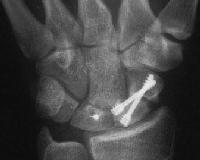

1. Nondisplaced fracture in a surgeon who declined continuous immobilization.

Click for larger image

One week after screw stabilization using a limited dorsal approach, he was back operating, but splinted when not scrubbed. These films are one month post op: no visible fracture.